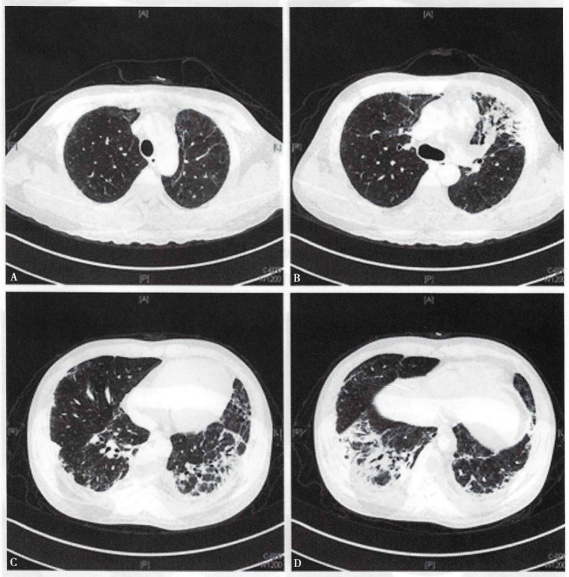

2016年12月中旬患者无诱因出现咳嗽,初为白痰,后为黄痰,量少,伴左侧季肋部疼痛和胸闷不适,未作特殊处理。12月27日患者可疑受凉后出现发热伴神志淡漠,体温最高39.1℃,来我院急诊,查尿隐血阴性,肌酐128 μmol/L,白细胞计数15×109/L;胸部CT(2016年12月28日)提示两肺磨玻璃影伴多发斑片密度增高影,左侧明显(图1)患者要求去外地就诊,拒绝住院。12月30日夜间再次高热,伴意识不清,再次来我院急诊查血常规:CRP 319 mg/L,白细胞11.8×109/L,体温39.5℃,予气管插管呼吸机辅助呼吸,收入RICU。

图1 患者胸部CT

入院后考虑患者有可疑受凉诱因,长期使用激素,WBC及CRP升高,两肺片状影,予比阿培南、莫西沙星及伏立康唑抗感染治疗,考虑重症肺炎。胸部CT可见局部胸膜下线及牵拉性支气管扩张(图1),感染继发或合并两肺弥漫性病变可能,予甲泼尼龙120 mg,bid,静脉滴注,并完善自身抗体、细胞免疫等检验。